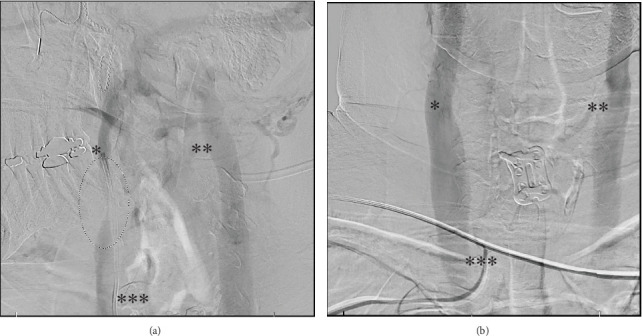

Jugular venous compression syndrome (JVCS) is caused by internal jugular vein compression, leading to headaches, neck discomfort, tinnitus, vertigo, confusion, and blurred vision. These impairments can diminish functional outcomes and compromise quality of life for patients. Literature-based treatments focus on surgical approaches and do not include chemodenervation. However, chemodenervation may be an additional treatment modality to consider. We present the first published case of chemodenervation utilized to successfully treat debilitating neck pain, headaches, and vertigo symptoms for JVCS, resulting in improved functionality and quality of life. This chemical denervation to the anterior neck musculature was trialed in hopes of avoiding surgical intervention. After three treatments, significant symptomatic relief with improved ability to work, improved performance of activities of daily living, and enhanced quality of life were noted. Educating physicians about JVCS and the various treatment modalities available is essential, as less invasive treatment options may not only become available to assist with the functional component of the condition but could also serve as potential alternatives to surgical and endovascular management in carefully selected patients, with the goal of optimizing function and improving quality of life among patients.